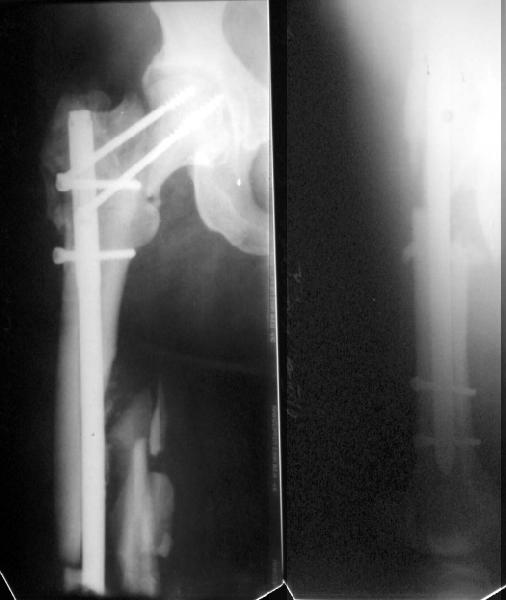

I agree with your assessment re: the neck, and think that ORIF of the femoral shaft is a good option. However, why not address the shaft component with a retrograde nail (AAOS OKU Trauma 1996)? You could perform the osteotomy in the usual way, secure the side plate to the proximal shaft initially with unicortical screws, complete the retrograde nailing procedure, then re-secure the side plate with bicortical screws directed around the nail. This would eliminate your concerns regarding the stress riser, and might be more practical then ORIF in this obese patient. I haven't done this with proximal femoral osteotomies per se but I've done it for shaft fractures with certain associated femoral neck or intertrochanteric fx patterns treated with a retrograde nail and DHS.

CB> One potential problem with recommending treatment options for the femoral neck nonunion is that we have no idea what the femoral neck alignment looks

This view was obtained in abduction + ext. rotation.

A subtrochanteric osteotomy was performed (a bit distally), after compression the lower crew was replaced with 3 monocortical. Then retrograde reaming was performed and UFN 12 mm was inserted and locked statically (with proximal screw through the plate). The neck gap looks well compressed. Image attached. Comments are welcome.